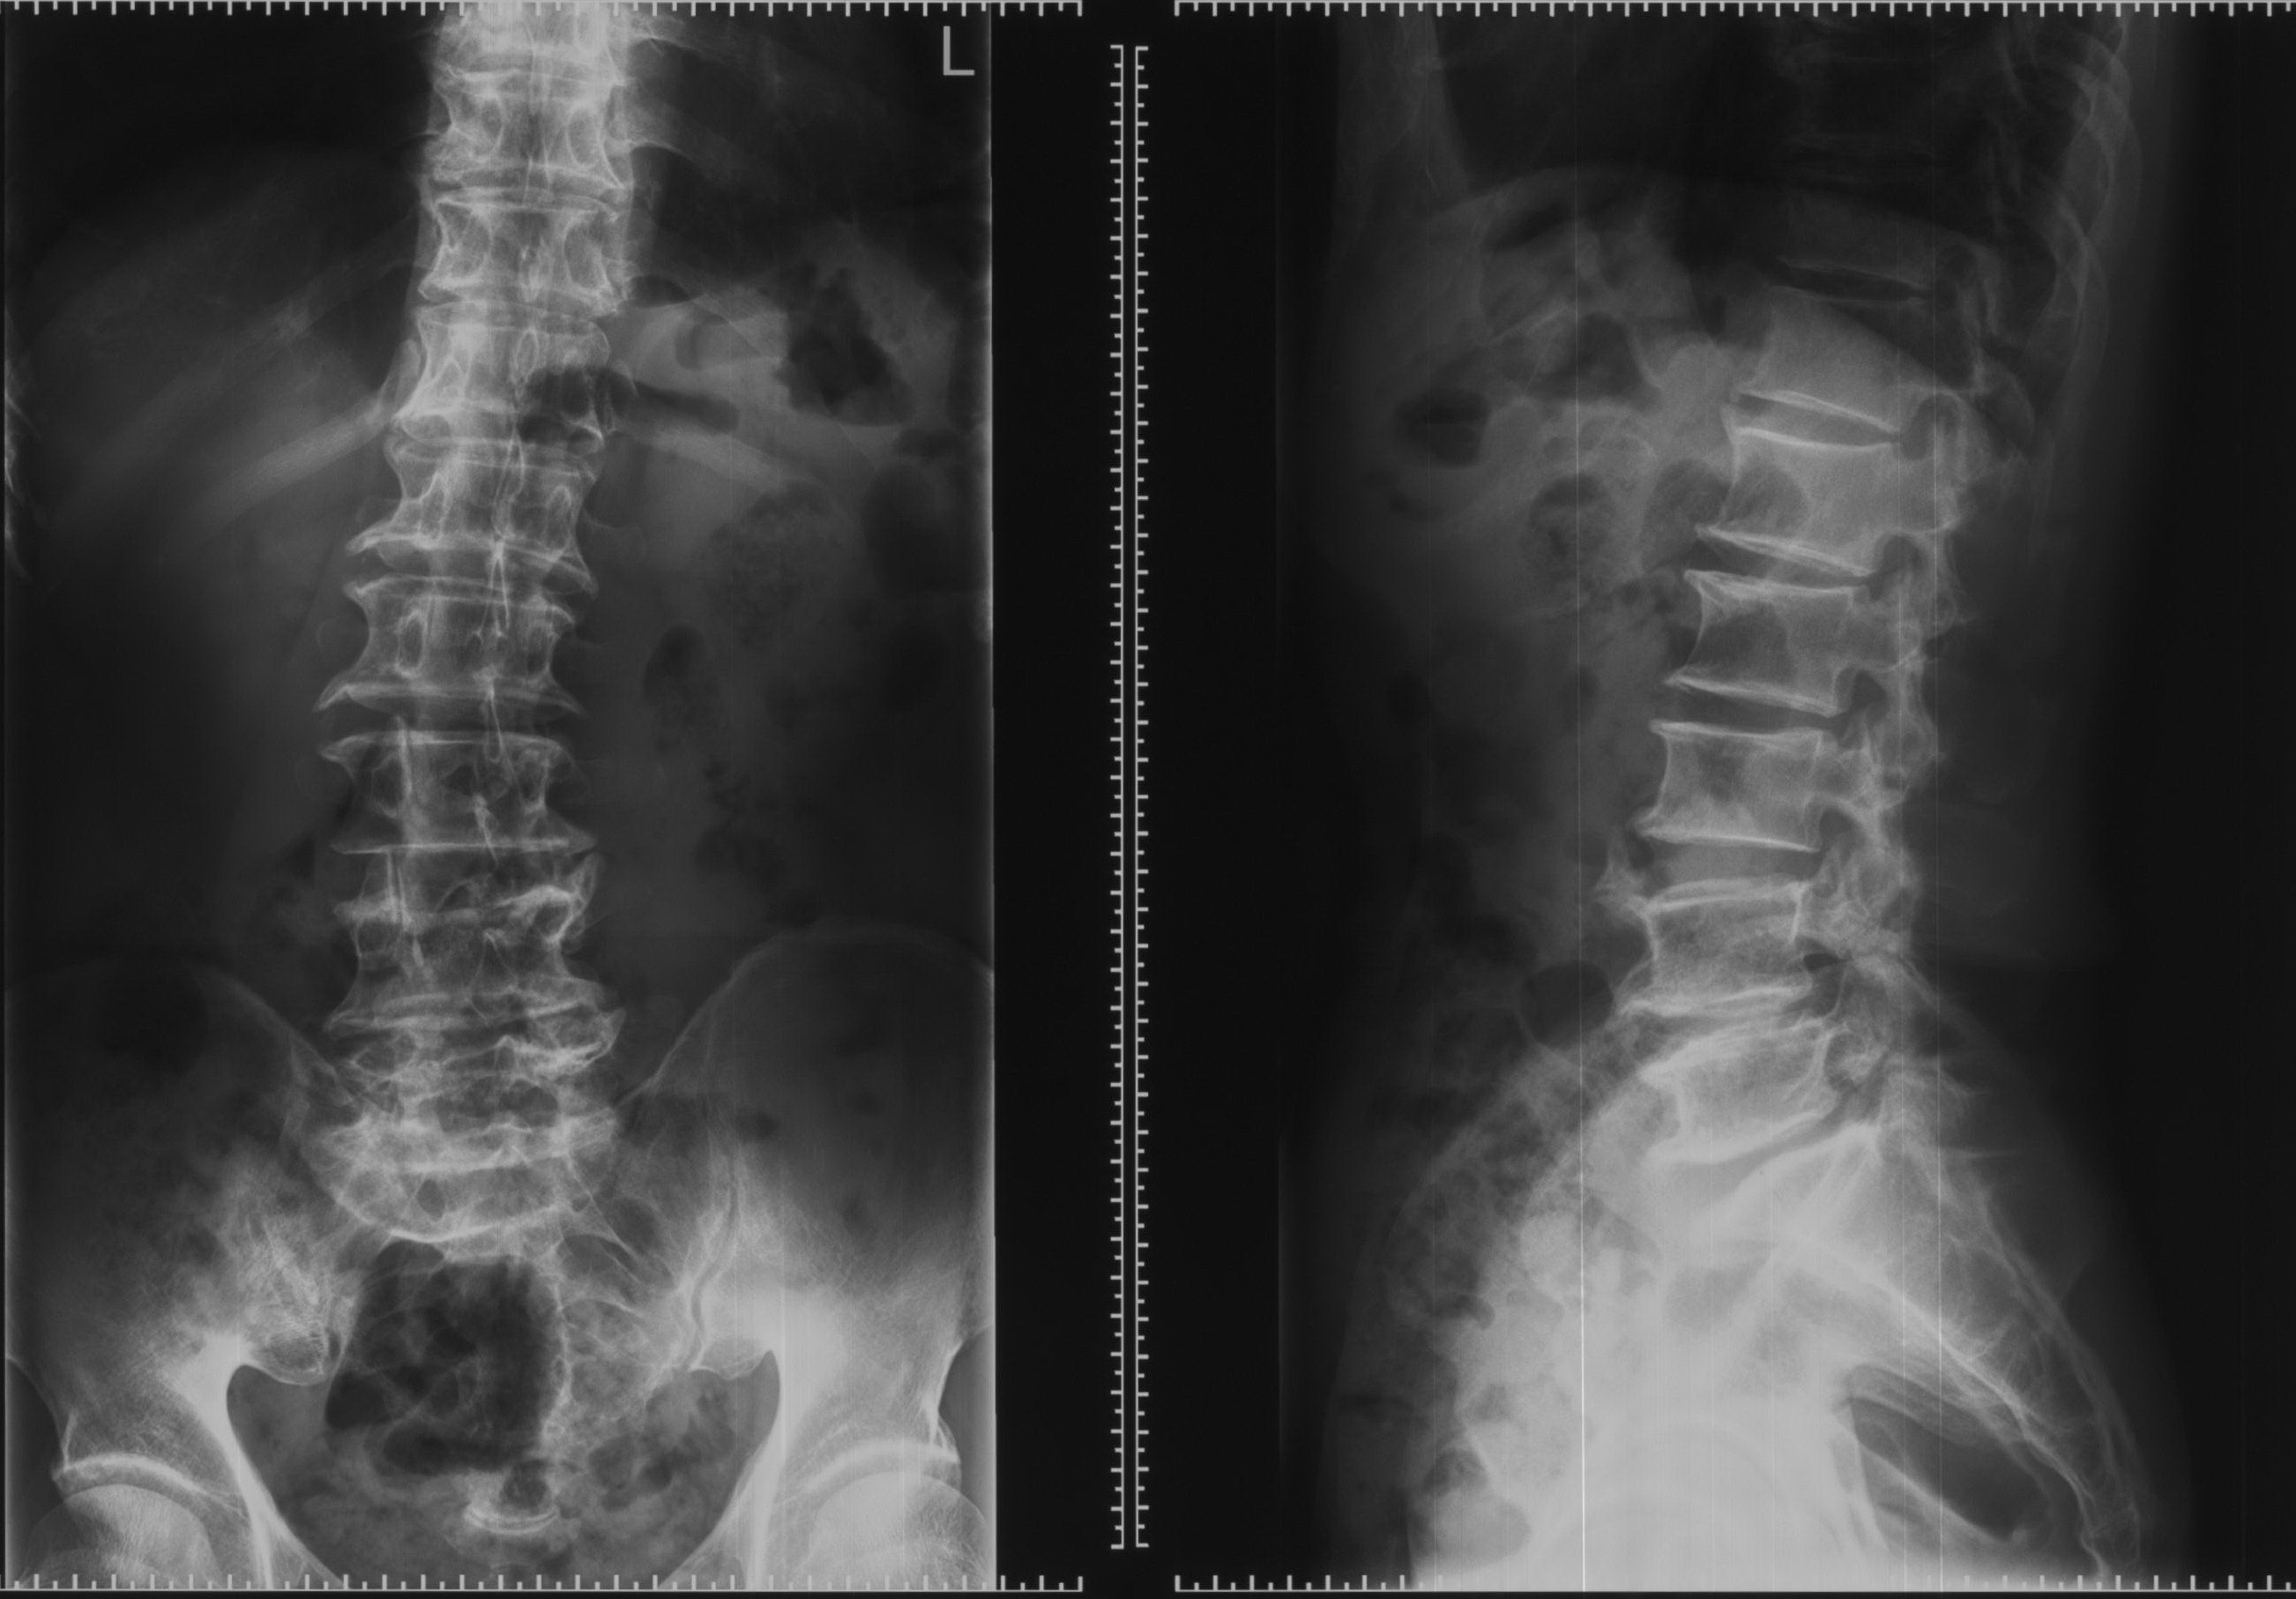

腰椎间盘突出